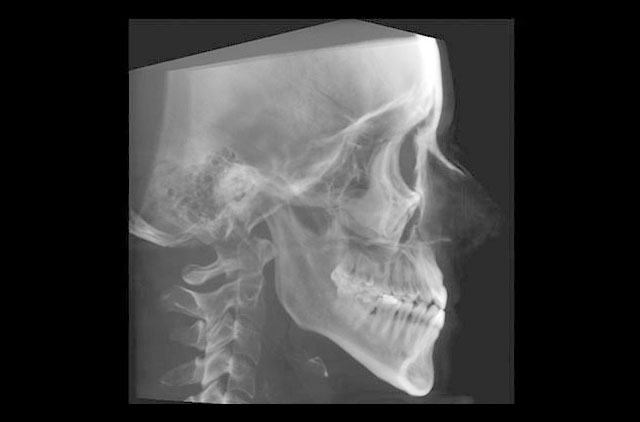

-Lateral de Craneo (LC) 8 x 10¨

-Lateral de Cráneo 8x10" (LC)

-Lateral de Cráneo 10x12" (LC)